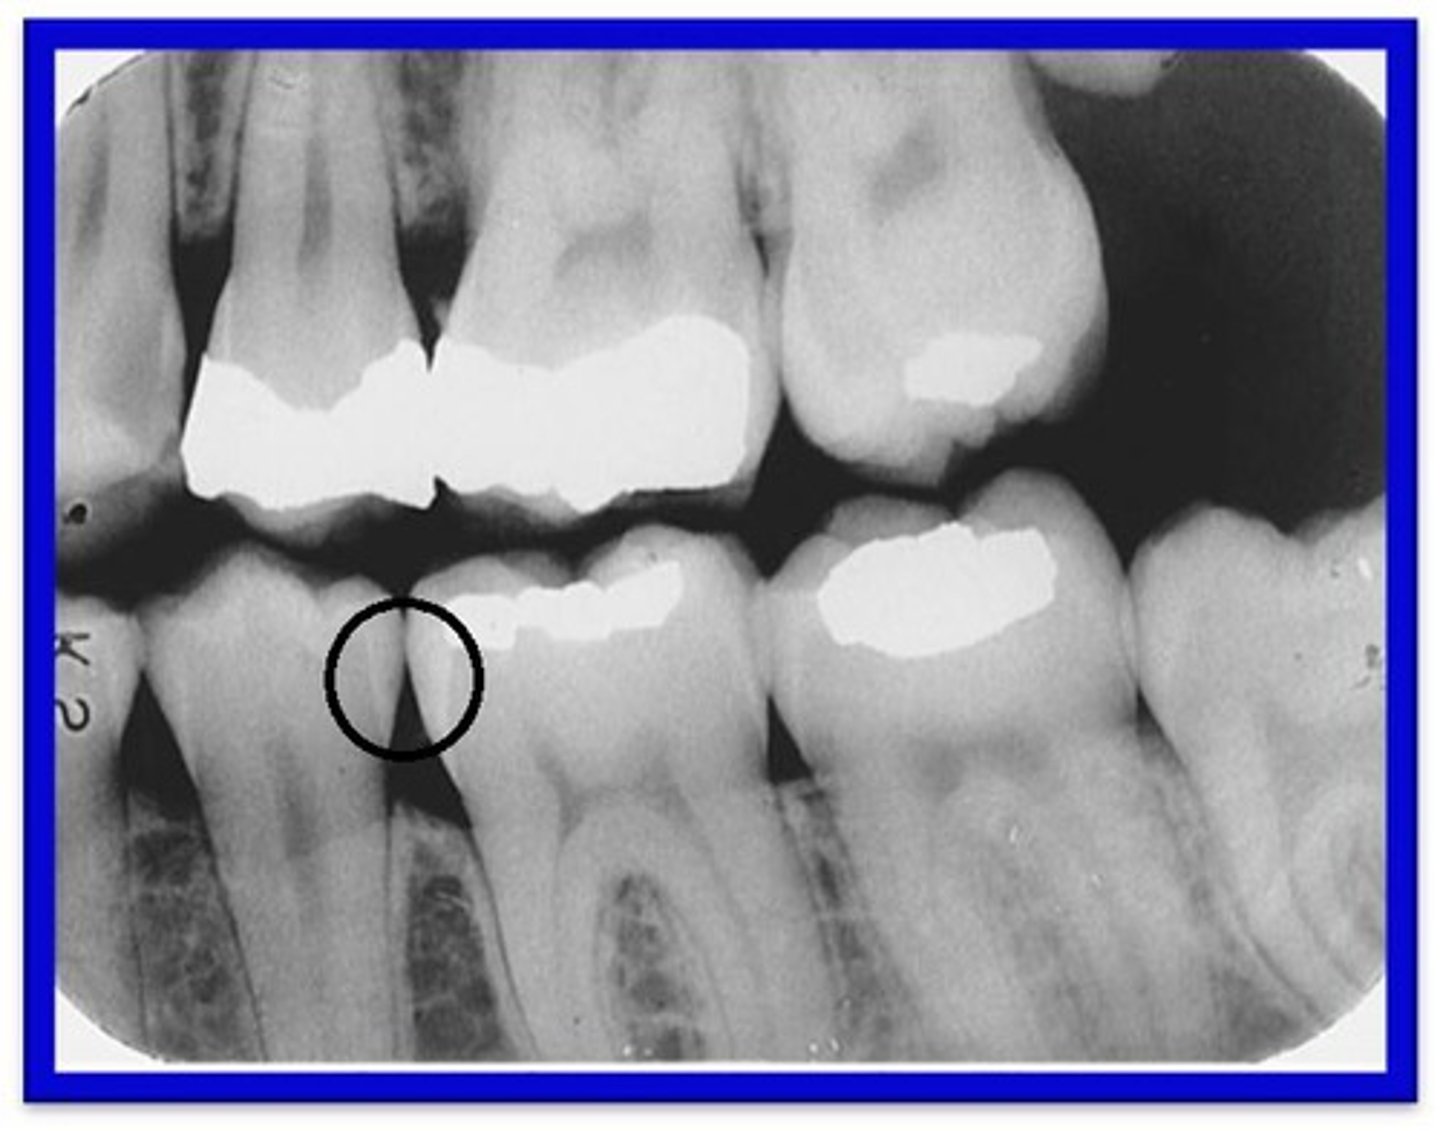

How do Interproximal Caries apppear?

Between 2 adjacent surfaces; typically seen at/just below the contact point. Triangular pattern begins at enamel.

What are Incipient Interproximal Caries?

Extends less than halfway through the thickness of enamel. Class I

What are Moderate Incipient Caries?

Extends more than halfway through enamel but does not involve the DEJ. Class II

What are Advanced Incipient Caries?

Extends to or through the DEJ and into dentin but does not extend into dentin more than half the distance toward the pulp. Enamel and Dentin. Class III